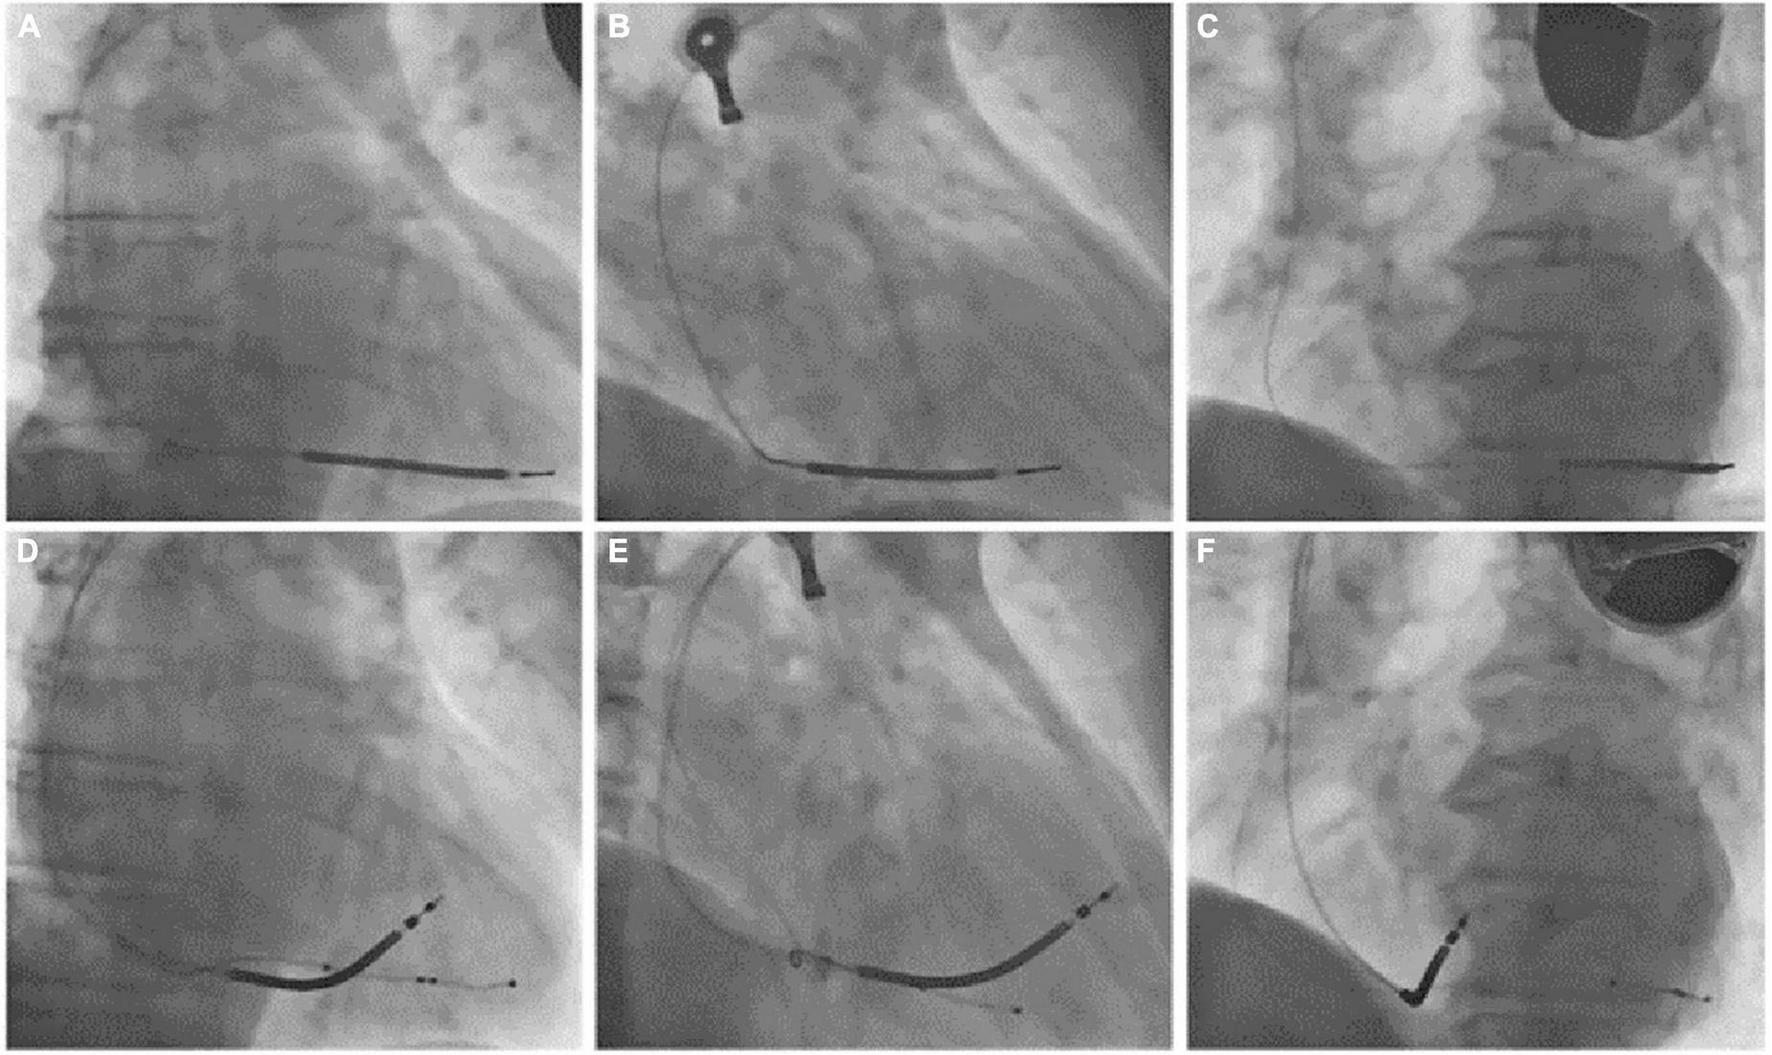

FIGURE 3

(Superior row) PA (A), RAO 30° (B), and LAO 45° (C) fluoroscopic views of the previously implanted single chamber cardioverter defibrillator with a single coil passive fixation defibrillation lead. (Inferior row) PA (D), RAO 30° (E), and LAO 45° (F) fluoroscopic views after lead extraction and the reimplantation of a new single-coil active fixation defibrillation lead on the mid portion of the interventricular septum and a coronary sinus quadripolar passive fixation lead for cardiac resynchronization therapy. PA, posteroanterior; RAO, right anterior oblique; LAO, left anterior oblique.

Phrenic nerve stimulation is a potential CIEDs complication, particularly in case of CRT with left ventricular pacing, due to the anatomic contiguity of the phrenic nerve to the lateral wall of the left ventricle. Direct diaphragmatic stimulation has also been hypothesized for LV pacing leads. PNS was more familiar with unipolar and bipolar coronary sinus leads due to the limited number of pacing configurations with such leads (3, 4). Contemporary quadripolar leads have markedly improved PNS management (5–8). However, in our patient, PNS was related to single-chamber ICD, a less common event. PNS after non-CRT devices implantation was previously reported following RVOT pacing (9) and as a consequence of lead fracture in subclavian crush syndrome (10). We excluded lead failure with fracture or insulation defect because lead parameters were in the range of normality. We excluded ventricular perforation for the same reason and for the absence of pericardial effusion. Therefore, we suspected inadvertent and erroneous lead malposition in a coronary sinus branch, confirmed by CXR. The 12-lead ECG obtained during hospital stay showed a RBBB with superior axis morphology of the paced QRS complexes further corroborating CXR findings (Figure 1B). The exact incidence of inadvertent lead malposition during CIEDs implantation remain unknown and is probably underestimated. A retrospective observational study reported an estimated incidence of inadvertent lead malposition of about 0.3% mainly due to endocardial left ventricular pacing through a patent foramen ovale (PFO), an atrial septal defect (ASD), or inadvertent arterial cannulation (11). A misplaced lead in a coronary sinus branch was the cause of inadvertent lead malposition in only one patient in the study cohort. Our case demonstrates the importance of accurate intraprocedural fluoroscopic and electrocardiographic evaluation of pacing and defibrillation leads during CIEDs implantation, and the necessity of specific training of radiologists in the evaluation of CIEDs related CXR. Anterior oblique fluoroscopic views during CIEDs implantation, particularly left anterior oblique (LAO) view, may prevent the inadvertent placement of a right ventricular lead in the coronary sinus (Figure 4).